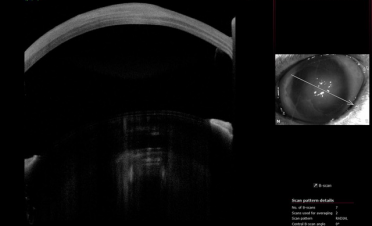

Se realizó una tomografía de coherencia óptica (OCT) para determinar el espesor de la córnea. En las imágenes se puede ver cómo el espesor de la córnea de Bagheera estaba aumentada de tamaño por la inflamación provocada por la infección.